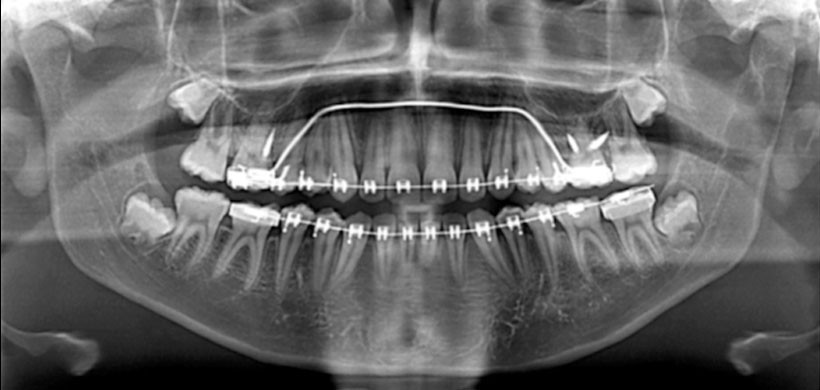

Así mismo refería no tener historia de trauma en el área maxilofacial. En la evaluación de rutina con una radiografía panorámica se reveló una radiolucidez en la zona de la rama y cóndilo mandibular izquierdo (Fig. 1).

Figura1: Radiografía panorámica